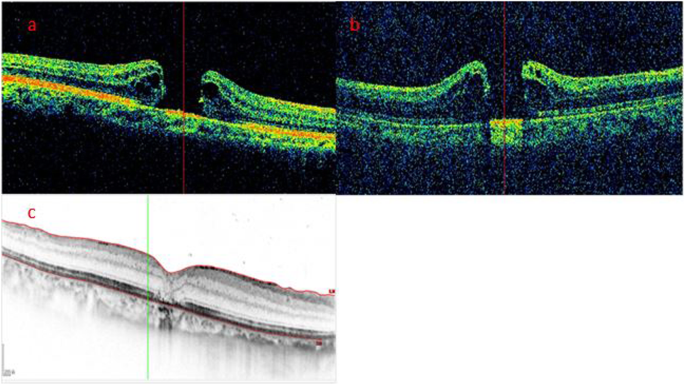

Case 3: A representative negative case. a The preoperative SD-OCT image showed a MH without a foveal flap in a 67-year-old woman. b iOCT showed neither foveal flap nor vertical pillars of tissue at the edges of the hole after ILM peeling. c Postoperatively at 6 months, SD-OCT showed hole closure without restoration of the ONL. The bridging tissue was hyperreflective. The BCVA was 0.15

According to the morphological characteristics of the hole edge as imaged by iOCT after ILM peeling, all patients were divided into three groups. In the Hole-Door group, iOCT revealed vertical pillars of tissue that projected into the vitreous cavity from the edges of the hole (Fig. 1). In the Foveal Flap group, iOCT imaged a preoperative foveal flap that adhered to the hole edge after ILM peeling (Fig. 2). In the Negative group, iOCT imaged neither hole-door nor foveal flap features (Fig. 3).